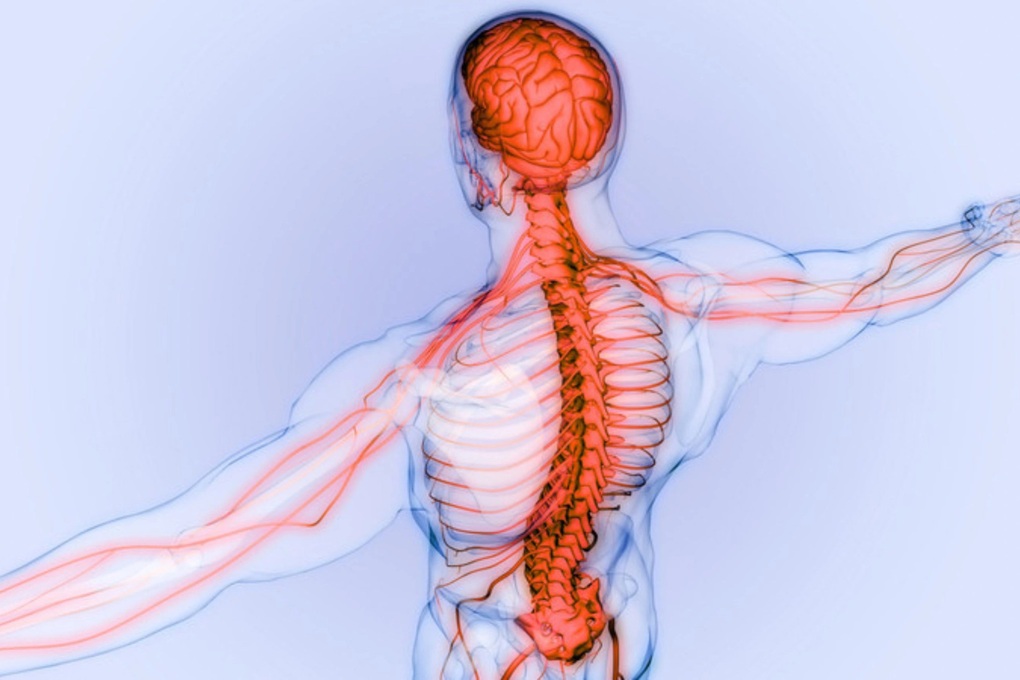

Không giống như các dạng đau do tổn thương cơ, xương hay khớp, đau do nguyên nhân thần kinh mạn tính (đau mạn tính) không để lại vết thương hữu hình nhưng lại bào mòn sức khỏe thể chất, khiến người bệnh mệt mỏi, mất ngủ và suy giảm tinh thần nghiêm trọng.

Theo các bác sĩ, đau mạn tính hình thành khi dây thần kinh bị tổn thương, viêm hoặc chèn ép, khiến các tín hiệu đau truyền liên tục hoặc sai lệch về não. Tình trạng này kéo dài làm hệ thần kinh hình thành “ký ức đau”, từ đó phản ứng mạnh trước cả những kích thích rất nhỏ.

Nhiều bệnh nhân mô tả họ chỉ cần chạm nhẹ vào vùng da cũng cảm thấy đau buốt, hoặc cơn đau xuất hiện dù không có bất kỳ tác động nào. Chính đặc điểm này khiến đau mạn tính khó đáp ứng với thuốc giảm đau thông thường và dễ dai dẳng hơn so với các dạng đau khác.